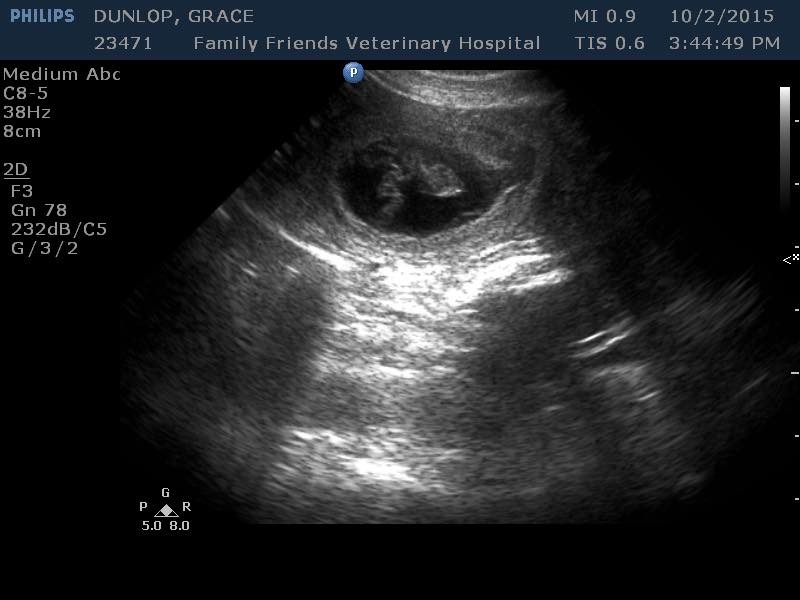

It’s a YES!!! He saw at least 8 babies on the Grace ultrasound. We are SO EXCITED BUT THE WAIT is going to be murder!! We have been trying for a year and a half and it appears the problem was poor Horace had an enlarged prostrate. Who would have ever guessed that at his young age. Hope will make sure he’s in tip top shape for future breeding so. I’m not taking any more Grace deposits, but am taking Rosalie ( Dark color babies I think) and Dottie ( red and white and black and white) all will give us fabulous colors, we love unique!!

I get Harlee off the bus a few times a week, we come to the park to play with the dogs and the kittens ( I took two of Harlees kittens that were at her moms house) it’s usually a little warmer and dryer by then so we have a good romp😀 Girls are always happy to see her. Rosalie is getting a belly about a week early which usually means lots of babies. I am SO GLAD we found this new vet in Grand Rapids. What a fabulous place, they do grooming, boarding, day care. Prices are reasonable and everyone SO NICE! If you’re in area you should try FAMILY FRIENDS VET HOSPITAL 6555 28th St 616.575.6520 Michigan State recommended them to my vet for reproductive services, turns out Rosalie ovulates late and we were giving up too early. Grace goes tomorrow for an ultrasound to see if she has babies. I honestly don’t know, one minute I think yes, then next minute no (sigh) I need to know😁 And the people who sent deposits are all eager to know!!! Stand by for NEWS!